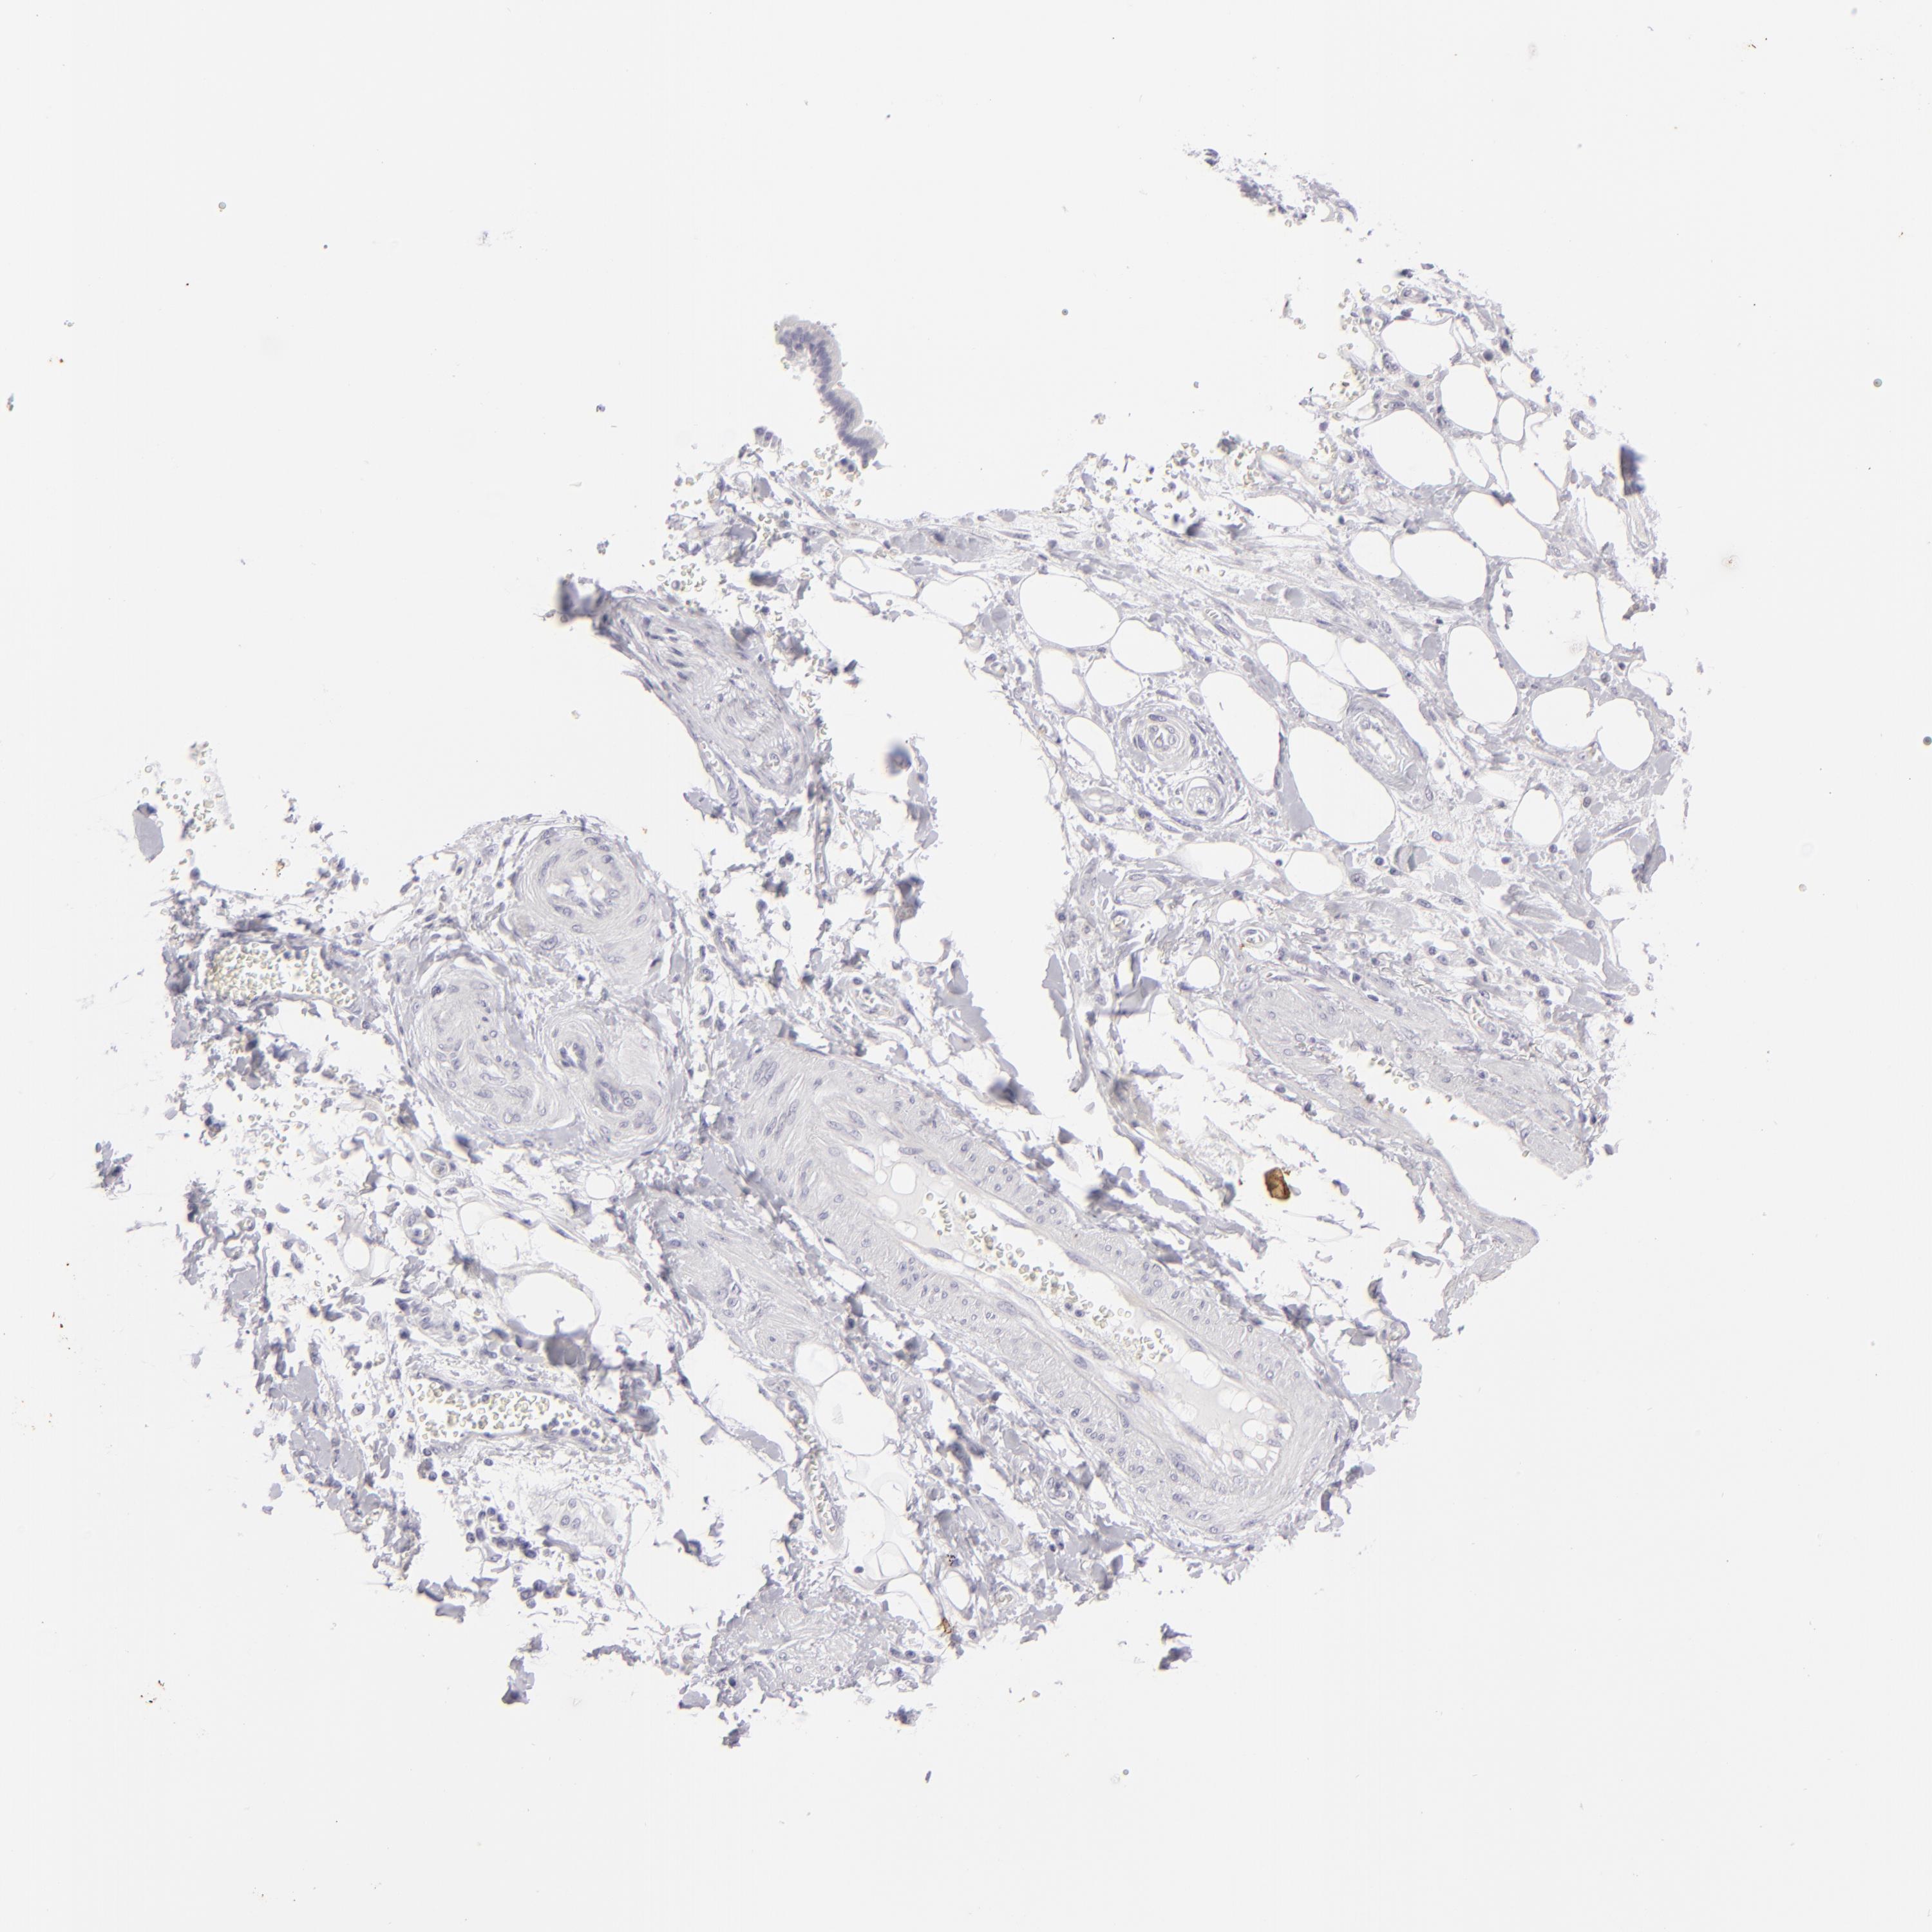

PANCREATIC CANCER - Protein expressioni

A mouse-over function shows sample information and annotation data. Click on an image to view it in a full screen mode. Samples can be filtered based on level of antibody staining by selecting one or several of the following categories: high, medium, low and not detected. The assay and annotation is described here.

Note that samples used for immunohistochemistry by the Human Protein Atlas do not correspond to samples in the TCGA dataset.

Antibody stainingi

Antibody staining in the annotated cell types in the current human tissue is reported as not detected, low, medium, or high, based on conventional immunohistochemistry profiling in selected tissues. This score is based on the combination of the staining intensity and fraction of stained cells.

Each image is clickable and will lead to virtual microscopy that enables deeper exploration of all samples and also displays staining intensity scores, fraction scores and subcellular localization as well as patient and tissue information for each sample.

Antibody HPA017917

Antibody HPA062908

Antibody CAB002153

Adenocarcinoma, NOS